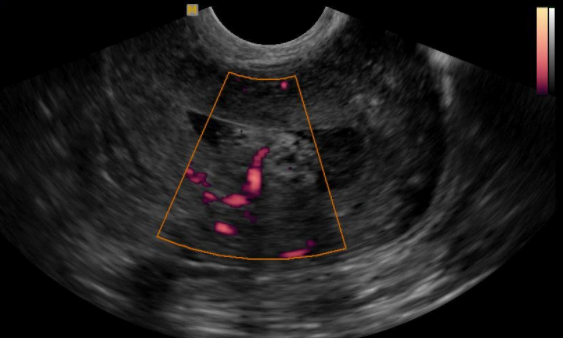

O diagnóstico do pólipo endometrial na maior parte das vezes é realizado por meio do ultrassom transvaginal.

Menopausa, tamanho do pólipo, espessura endometrial, tipo e intensidade de vascularização e a história clínica são fatores que devem ser avaliados e que contribuem para o risco de malignidade.